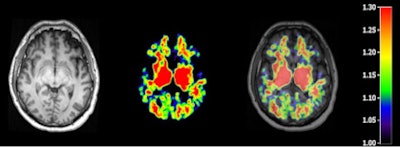

In this study, PiB-PET was performed postmortem on 15 subjects (median age, 33 years) with moderate to severe traumatic brain injury and 11 healthy controls (median age, 35 years) with no symptoms, signs, or diagnoses of neurological disease or abnormalities as shown on a brain MRI. The healthy participants also had a normal score on a mental exam.

To help segment areas of the brain into tissue classes and delineate anatomical regions of interest, participants also underwent an anatomical 3-tesla MRI scan using a Tim-Trio scanner (Siemens Healthcare).

The researchers also measured the PiB distribution volume ratio and standardized uptake value (SUV) ratio in the PET images, specifically looking at cortical gray matter, white matter, and multiple cortical and white-matter regions of interest, as well as striatal and thalamic regions of interest. Those regions of the brain are associated with executive function and memory and are likely to show early signs of Alzheimer's disease.

The analysis found that subjects with traumatic brain injury showed significantly greater PiB distribution volume ratios in cortical gray matter and in the striatum, but not in the thalamus or white matter, compared with the control group.

Increases in PiB distribution volume ratios in patients with traumatic brain injury were also seen across most cortical subregions and were replicated in SUV ratios. Control subjects, meanwhile, showed relatively low PiB binding, predominantly in the central white-matter and deep gray-matter structures.